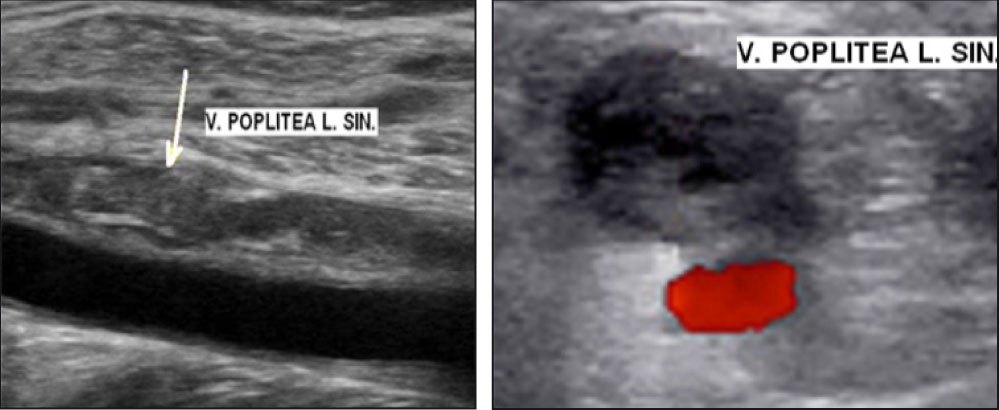

Komplikace pátý pooperační den: rozvoj levostranné popliteální HŽT (verifikace pomocí duplexního ultrazvukového vyšetření [DUZ], viz obr. 1). Předoperačně byl pacient hodnocen z hlediska rizika TEN jako nízkorizikový. Pooperačně tedy nepodávána žádná preventivní tromboprofylaxe. Laboratorně hodnota D-dimerů 785 µg/l [1..190], současně průkaz trombofilního geneticky determinovaného stavu – FV leidenská heterozygotní mutace (FVL het.). Dále laboratorně jaterní funkce v normě, renální parametry v normě, MDRD (Modification of Diet in Renal Disease) 1,28 ml/s [1..1,5]. Iniciálně byl podáván jako antikoagulační terapie Eliquis tbl. 2× 10 mg (10 dní), dále pokračováno s dávkou 5 mg 2× denně.

Obr. 1 – DUZ: iniciální nález pooperační levostranné popliteální HŽT